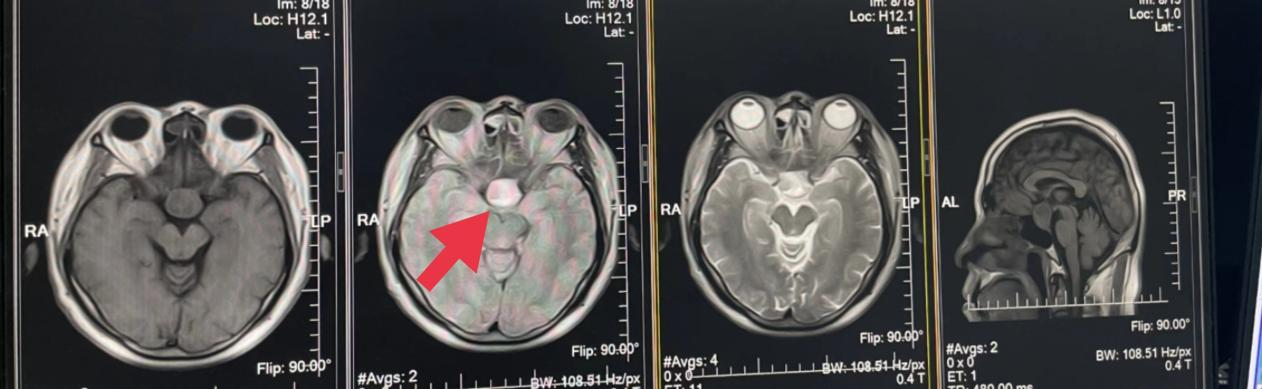

10、**男士,62岁

于2023年8月10日在银川仁泰体检部体检,脑核磁检查提示:矢状位显示蝶鞍增大,鞍上池内T2WI、FLAIR示18.5*23mm等高信号、T1WI示等信号影。双侧上颌窦、筛窦、蝶窦粘膜增厚,考虑脑垂体腺瘤。建议客户到综合医院专科进一步检查。2023年8月25日跟踪回访,客户已到北京协和医院复查,明确诊断脑垂体瘤,准备手术治疗。